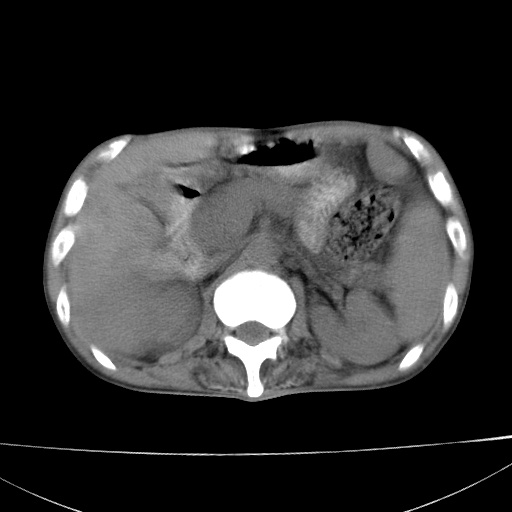

患者 男  41岁,右上腹痛伴腹泻10天,8年前有乙肝,本次b超查肝右叶占位来做ct ,请会诊!

肝硬化\\脾大\\门静脉高压,胃底静脉曲张可能性大.肝右叶肝癌肝内转移,建议增强.左侧小结石.

肝右叶肝癌肝内转移,建议增强

支持肝癌伴肝内转移,脾大,门静脉高压,胃底静脉曲张。

1)考虑肝癌;建议行ct增强扫描检查。2)脾大,门静脉高压,胃底静脉曲张。3)左肾小结石。

1)考虑肝癌及门脉瘤栓,建议行ct增强扫描检查。2)脾大,门静脉高压,胃底静脉曲张。3)左肾小结石。

结合病史;考虑肝癌。门静脉高压,脾大。胃底静脉曲张。

1)考虑肝癌;2)脾大,门静脉高压,胃底静脉曲张。3)左肾小结石。建议行ct增强扫描检查。